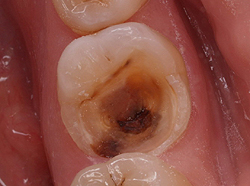

Не лікувалися карієс або неякісно пломбовані каріозні порожнини є вхідними воротами для патогенних мікроорганізмів. Продукти їх життєдіяльності і стають основною причиною пульпіту. Більшу частину пульпітів викликає гемолітичний і негемолітіческій стрептокок, тому при стрептококової ангіні і наявності нелікованого карієсу, може виникнути ускладнення у вигляді пульпіту. Стафілококи, лактобацили і інші мікроорганізми рідше стають причиною пульпіту.

Запальний процес починається з уже інфікованого ділянки, який знаходиться біля каріозної порожнини, далі мікроби і токсини проникають в кореневу пульпу. Іншою причиною пульпіту є травми зуба , В основному це відлам частин коронки, відколи емалі і переломи зуба . Рідше пульпіти виникають під впливом агресивних температурних і хімічних чинників.

Гострий вогнищевий пульпіт характеризується нападами болю, з чіткою локалізацією і тривалими проміжками интермиссии. Напади болю при гострому очаговом пульпіті в основному короткочасні, біль настає від впливу температурних подразників. Хворобливість посилюється в нічний час, що є характерним симптомом для всіх пульпітів. При обстеженні виявляється глибока каріозна порожнина, дно порожнини під час зондування болісно. Електровозбудімость пульпи знижена з того боку, в області якої локалізується вогнищевий пульпіт.

Пульпіт діагностують на підставі суб'єктивних скарг і інструментального огляду стоматолога . Під час інструментального огляду виявляється каріозна порожнина з розм'якшеним дентином, хвороблива реакція ураженого зуба на зміну температури. Перкусія при пульпіті майже завжди безболісна. Різка болючість спостерігається в місці, де каріозна порожнина максимально контактує з пульпою. Дані електровозбудімості ( електроодонтодіагностика ) і рентгенологічні дослідження дозволяють уточнити характер і глибину пульпіту.